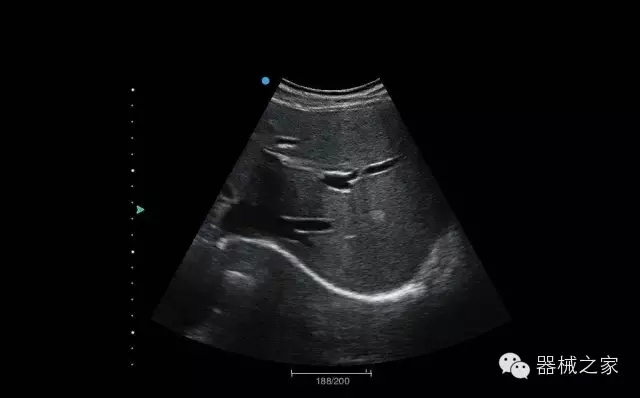

臍帶血流